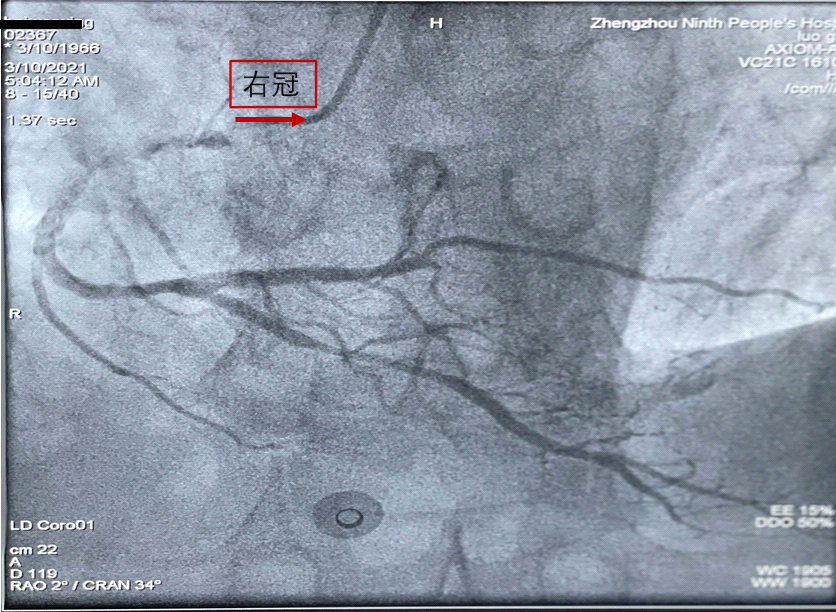

术后患者被送往CCU继续监测治疗。到达科室后患者出现胸闷、呼吸困难,面色青白、口唇紫绀,两肺满布干湿性啰音,指脉氧下降至89%,06:45突然出现呼吸心跳骤停,意识丧失,命悬一线!值班医师王彩歌及手术医师杜明远和值班护士立即对患者进行气管插管、胸外心脏按压等抢救措施,心脏中心赵明中主任、CCU余娟主任接到急救电话后紧急到达科室指挥抢救,杜明远医师快速完成桡动脉穿刺及颈内静脉穿刺置管,其他成员完成多次反复电除颤、药物升压、纠正心律失常、呼吸参数调整、床旁心脏彩超检查……CCU医护团队所有的抢救工作紧张有序地进行,医护人员各司其责,大家都很清楚,这是在与死神赛跑,需分秒必争。复苏20分钟后,患者仍未恢复自主心律,自主循环不能维持,瞳孔开始散大,此时患者病情已经十分凶险,陷入了深度昏迷状态,心率0、血压和指脉氧均测不出。为保证获得最佳治疗效果,余娟、赵明中主任当机立断启动ECMO(体外膜肺氧合)。在等待ECMO抢救组到来期间,CCU医护团队抢救不停歇,为保证有效心肺复苏,全科医护人员不间断地竭尽全力进行心脏按压,终于在07:48分,即抢救63分钟后患者心跳恢复,血氧饱和度逐渐维持在90%左右,血压在升压药物维持下71/50mmHg,生命体征仍不稳定,意识仍然处于深昏迷状态。此时ECMO抢救组也已迅速到位并顺利植入,植入后患者生命体征逐渐稳定,血压回升至87/57mmHg,指脉氧升至98%,自主循环初步稳定。目前患者病情正在逐步恢复中。

图:患者植入ECMO后